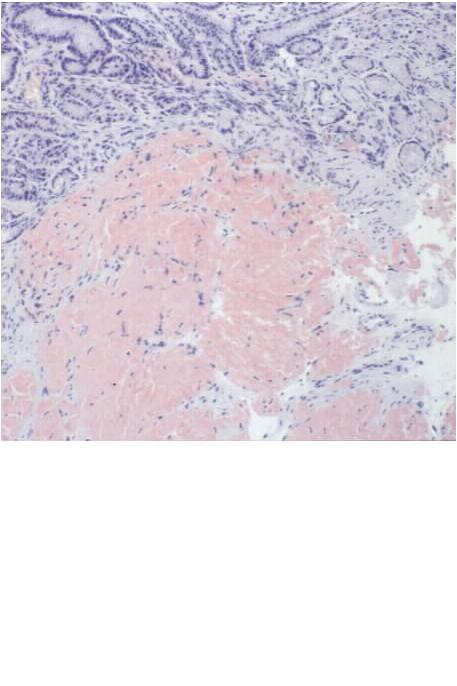

OMH 981706; Amyloidosis, stomach (HE stain [jpg.29KB]), (Congo red stain [jpg.37KB])

Amyloid deposition is confirmed by Congo-red stain with positive birefringence regarding the colonic and gastric specimens.

2. The heart is enlarged and abnormally stiff, which weighs 700 gram and, on cross sections, reveals marked dilatation of both the atriums and hypertrophy of both the ventricles, but no scarring of the myocardium is noted ([jpg.21KB]). The lumen of the left ventricle is moderately dilated. Fresh coagulation mass, partly thrombotic, is adherent to the wall of the right auricle. The circumferences of all the four valves are remarkably increased, resulting in insufficiency state. Arteriosclerotic changes of the coronary arteries are minimal to the naked eye, without narrowing. Microscopic examination reveals patchy and diffuse deposition of amorphous eosinophilic extracellular substance (HE stain [jpg.45KB]) that is stained pink or orange by Congo red stain and shows rather moderate birefringence by polarizing microscopy ([jpg.13KB]). Myocardial fibers show atrophy and degeneration.

b. The esophagus, stomach and intestines are otherwise unremarkable to the naked eye than mild mucosal petechia of the stomach with bloody content that measures about 100 ml in volume. Microscopic examination reveals diffuse and patchy deposition of amyloid substance mainly in the smooth muscle layer but also in the muscularis mucosae and submucosa of those organs (Sigmoid, HE stain [jpg.26KB]).